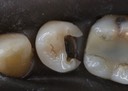

Joe Cha #18 amalgam removal

Joe Cha #18 prep